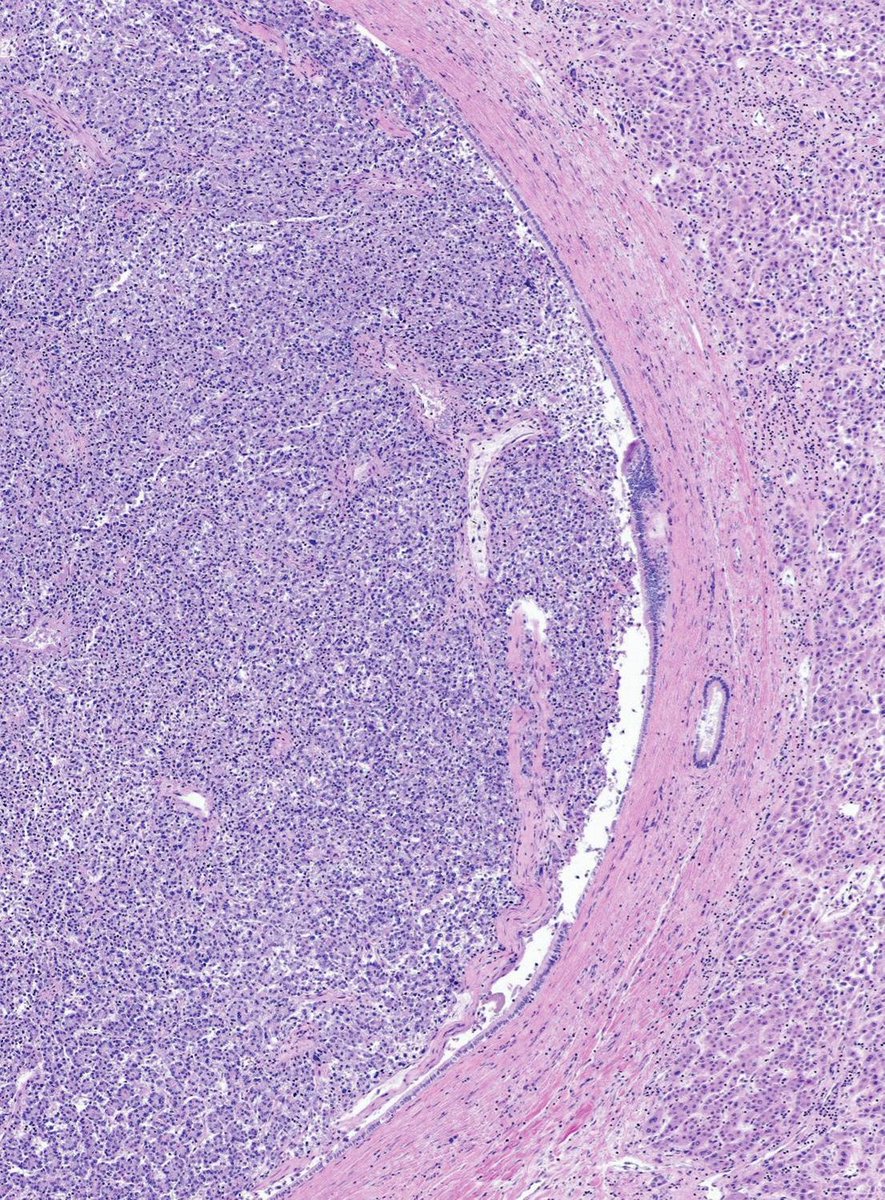

Let’s review special morphologic patterns of invasive breast carcinoma (IBC) this week! Case of Medullary Pattern 🔬 Medullary IBC shows well-circumscribed high-grade carcinoma with syncytial growth and prominent tumor-associated lymphocytes. #PathX #PathTwitter #breastpath

Let’s review special morphologic patterns of invasive breast carcinoma (IBC) this week!

Case of Medullary Pattern 🔬

Medullary IBC shows well-circumscribed high-grade carcinoma with syncytial growth and prominent tumor-associated lymphocytes.